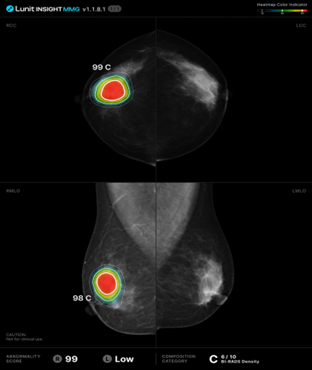

그림2.png [그림2] 출처 : Lunit Inc.

INSIGHT MMG는 유방 엑스레이인 맘모그래피 이미지를 분석하는 소프트웨어다. 이 소프트웨어는 유방암을 포함한 유방 질환의 징후를 탐지하고, 의료진에게 알려준다. 유방암 조기 발견에 특히 중점을 두고 있다.